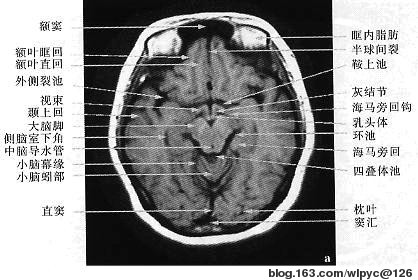

内囊歌诀

内囊并非一个囊,交通枢纽恰称当;

豆尾与丘之间是,投射纤维聚多方;

水平切面拐角形,前后二脚膝中央。